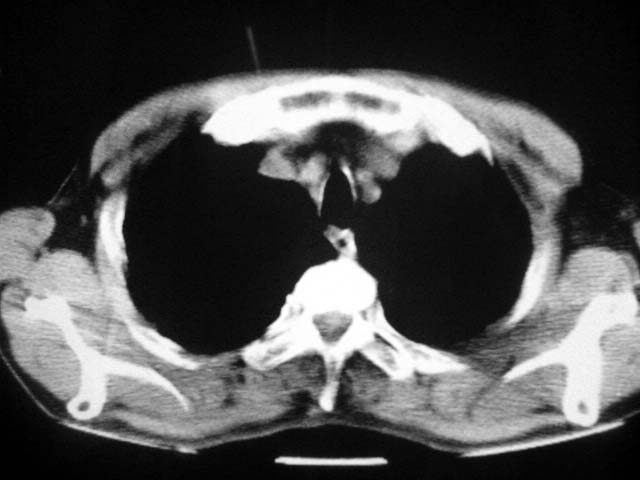

以下是引用zjzjr在2007-9-4 17:00:00的发言:[br]双上肺继发型结核伴左上肺空洞形成.慢性支气管炎伴肺气肿.

以下是引用liuzheng_9326在2007-9-4 16:23:00的发言:[br]痰检未见结核菌, 治疗后症状好转。图像符合陈旧性结核伴感染。